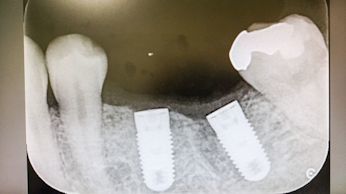

治療が不可能で抜歯をしなければならない状態にまでなってしまっている歯が複数に及ぶ患者さんもいらっしゃいます。

歯は一生ものです。

歯科医院は治療する所だけでなく、

歯を一生大事に使えるよう管理していく所でもあるのです。